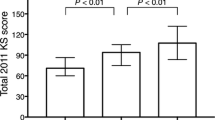

KSS 2011 scores except patient expectation were significantly improved postoperatively (Table 1). The average preoperative extension angle was significantly improved postoperatively, and preoperative flexion angle was maintained at 2 years after TKA. Regarding limb, femoral and tibial alignment, neutral alignment was achieved postoperatively. Preoperative alignment had no significant correlation with postoperative alignment in HKA (p = 0.166), FMA (p = 0.540), and TMA (p = 0.501) (Fig. 2).

The average residual varus–valgus imbalance was 2.8° (SD = 2.8°) varus in extension and 1.3° (SD = 4.0°) varus in flexion. The average varus–valgus angles were kept varus in extension and flexion, respectively (Fig. 3). The average extension gap was smaller than the flexion gap. The average extension and flexion gaps were 9.4 mm (SD = 2.5 mm) and 12.7 mm (SD = 2.8 mm), respectively. The average thickness of polyethylene insert was 10.0 mm (SD = 1.4 mm). The distribution of the laxity in flexion was more variable than in extension (Figs. 4, 5). Analyzing correlation with the alignment and the gap angle and joint laxity, the delta HKA angle had significant correlation with the joint gap angle, and the preoperative TMA and delta TMA had significant correlation with the laxity in extension (Table 2). Larger correction angle of limb alignment showed more varus joint gap in extension, and larger varus deformity and correction angle of the tibia showed more laxity in extension.

In comparison, according to the varus–valgus joint gap angle in extension, no valgus imbalance group was found, and no significant differences in patient demographics, preoperative and postoperative clinical outcomes were observed among the groups except BMI and preoperative HKA angle (Table 3). In comparison, according to the varus–valgus joint gap angle in flexion, there were no significant differences in patient demographics, preoperative and postoperative clinical outcomes among the groups (Table 4).

In comparison, according to the knee laxity in extension, there were no significant differences in clinical outcomes among the groups (Table 5). In comparison, according to the knee laxity in flexion, preoperative patient expectation had significant difference between moderate and loose groups and between moderate and over loose groups. However, no significant differences were observed in postoperative clinical outcomes (Table 6).

So far, it is still under discussion whether varus–valgus imbalance affects clinical outcomes. A previous study measuring the joint gap with a tensor device revealed achieving equalized rectangular gaps at extension and flexion did not influence 2-year postoperative clinical outcomes [14]. In several reports, however, asymmetrical gap balance affected negatively the University of California, Los Angeles activity level at 4 months, the postoperative knee flexion at 1 year, and Western Ontario and McMaster Universities Arthritis Index (WOMAC) score at 34 months, although these studies did not separately evaluate the knees with varus and valgus imbalance [10, 16, 32]. In the present study, the effect on clinical outcomes was analyzed at 2 years using KSS 2011 for consecutive knees with preoperative varus deformity. In extension, the groups with the residual varus and severe varus imbalance during TKA showed no significant differences in clinical outcomes including range of motion and KSS 2011 in comparison with the balanced group. However, the effect of valgus imbalance was unclear, because no knee showed postoperative valgus imbalance. In flexion, the groups with residual valgus, varus, and severe varus imbalance also showed no significant differences in comparison with the balanced group, although valgus imbalance was correlated with poor postoperative outcomes in several studies [24, 32]. The findings of the present study suggest that the asymmetrical gap seems to have no relation with early postoperative knee function and patient satisfaction. However, further research should be conducted to evaluate long term durability for the knees with asymmetrical varus–valgus balance, because 2-year follow-up is too short to comment on wear and aseptic loosening.